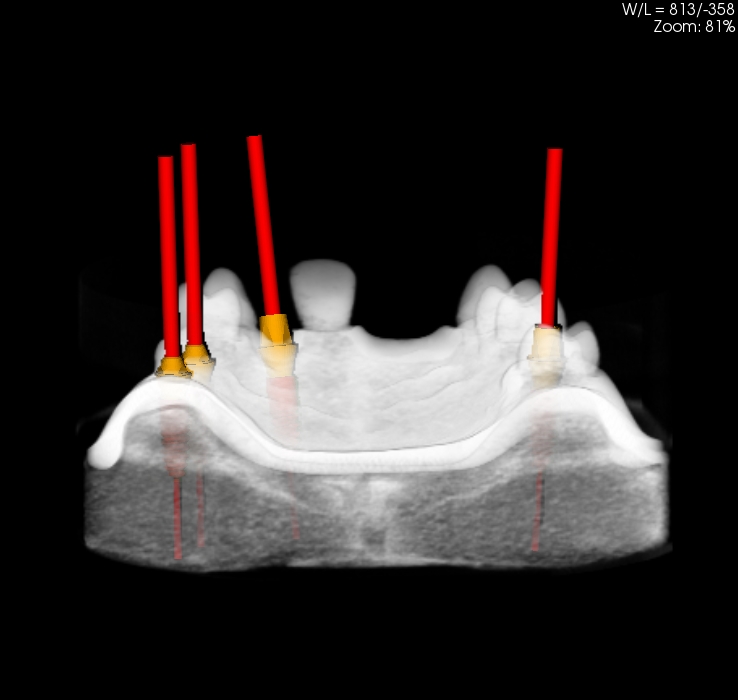

Oferujemy również szablony chirurgiczne przeznaczone do szkoleń z implantacji. Umożliwiają planowanie leczenia implantologicznego i przeprowadzenie szkoleń z wykorzystaniem plików CT, STL oraz druku 3D. Oferujemy nasze modele do szkoleń implantologicznych wraz z plikami DICOM i STL.

Pliki do wykonania szablonów można pobrać z naszej strony internetowej. Możemy je również dostarczyć wraz z modelami. Pliki te dostępne są dla modeli 10-1030, 10-3040, 10-3050, 10-5070,

Istnieje również możliwość dostarczenia szablomów w oparciu o pliki i informację o planowanej procedurze implantologicznej.

Model szczęki z zębami w pozycjach 11, 13, 14, 23, 24, 25 i 27, brakiem zębów w wygojonych pozycjach 21, 22, 26, 15, 16. Umieszczenie dwóch zagłębień imitujących niezagojone zębodoły w pozycjach 17 i 12 umożliwia ćwiczenie implantacji wczesnej i natychmiastowej. Wykonany jest z jednorodnego materiału o właściwościach zbliżonych do kości ludzkiej.  Model pokryty jest śluzówką, którą można nacinać i zszywać. Znakomicie nadający się także do  nauki implantacji odroczonej i planowania leczenia poekstrakcyjnego. Umożliwia również przedstawienie problemów związanych z prawidłowym umieszczeniem implantów pomiędzy koronami sąsiadujących zębów. Model można stosować w najbardziej popularnych na rynku fantomach jak i głowie fantomowej PROMEDICU 11-1000 jak również samodzielnie bez niego.

Poniżej znajduje się przycisk umożliwiający ściągnięcie pliku STL przeznaczonego do wykonanie szablonu do szkoleń implantacyjnych z użyciem modelu.

Numer katalogowy 10-5070